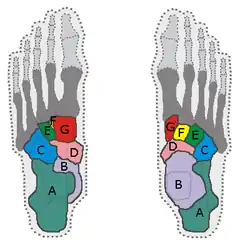

Squelette

Le squelette du pied est constitué de trois parties, d'arrière en avant : le tarse, le métatarse et les phalanges. Le tarse est constitué de sept os courts que l'on peut répartir en deux groupes : en arrière, le calcanéus (ou calcanéum) et le talus (ou astragale) ; en avant, l'os cuboïde, l'os naviculaire (ou scaphoïde tarsien) et les trois os cunéiformes (latéral, intermédiaire et médial). Les cinq métatarsiens sont des os longs qui forment le métatarse et relient l'os cuboïde et les trois cunéiformes aux phalanges des orteils.

On peut aussi diviser le pied selon une autre approche : l'arrière-pied, constitué du talus et du calcanéus ; le médio-pied, constitué de l'os cuboïde, de l'os naviculaire et des os cunéiformes ; l'avant-pied, constitué des métatarsiens et des phalanges.

Arrière-pied

L'arrière-pied est la portion postérieure du tarse. Il est constitué par le talus et le calcanéus, le talus étant au-dessus et légèrement médial par rapport au calcanéus, tout en étant plus court que ce dernier. Le talus est un des os de la cheville ; il s'articule en haut avec le tibia principalement, et aussi avec la fibula (ou péroné). Le talus s'articule également en bas avec le calcanéus sous-jacent, et son extrémité antérieure, située médialement dans le pied, s'articule avec un des os de la rangée antérieure du tarse, l'os naviculaire. Le calcanéus est l'os du talon, et c'est l'os le plus volumineux du pied. Il s'articule en haut avec le talus, au niveau de la portion antérieure de sa face supérieure. Le tiers postérieur de cette même face reçoit le tendon calcanéen (ou tendon achiléen) issu du muscle triceps sural du mollet. Le calcanéus est orienté en avant, en haut et latéralement ; son extrémité antérieure s'articule avec l'os cuboïde.

Médio-pied

Le médio-pied est la partie antérieure du tarse. Il est constitué de cinq os. Médialement, il y a une double rangée : il s'agit de l'os naviculaire en arrière et des trois os cunéiformes en avant. Latéralement, il n'y a qu'un os : l'os cuboïde. Concernant la partie médiale, l'os naviculaire s'articule donc : en arrière avec le talus, latéralement avec l'os cuboïde, en avant avec les os cunéiformes médial, intermédiaire et latéral. Ceux-ci occupent une position relative entre eux cohérente avec leurs noms et sont chacun en rapport en avant avec un des trois premiers métatarsiens. L'os cunéiforme latéral est par ailleurs articulé sur sa face latérale avec l'os cuboïde. La partie latérale du médio-pied est occupée par l'os cuboïde, qui s'articule donc : sur sa face postérieure avec le calcanéus ; sur sa face médiale, en arrière avec l'os naviculaire et en avant avec l'os cunéiforme latéral ; sur sa face antérieure, avec les quatrième et cinquième métatarsiens.

Avant-pied

L'avant-pied correspond au métatarse et aux phalanges. Le métatarse est constitué par les cinq métatarsiens, de manière comparable au métacarpe de la main. Les métatarsiens sont articulés au niveau de leur base avec : les os de la rangée distale du tarse, soit dans l'ordre les os cunéiformes médial, intermédiaire et latéral pour les trois premiers, et l'os cuboïde pour les deux derniers ; et avec la base du ou des métatarsiens adjacents. Au niveau de leur tête, en distalité, les métatarsiens sont chacun en rapport avec la base de chaque phalange proximale respective. Les phalanges du pied sont disposées de la même manière que celles de la main ; une phalange proximale est articulée en avant avec une phalange moyenne (dite phalangine), elle-même articulée en avant avec une phalange distale (dite phalangette). Tout comme pour la main, les premières phalanges ne sont que deux, la proximale et la distale. Enfin, chaque métatarsien et les phalanges correspondantes forment ensemble une même structure appelée rayon.